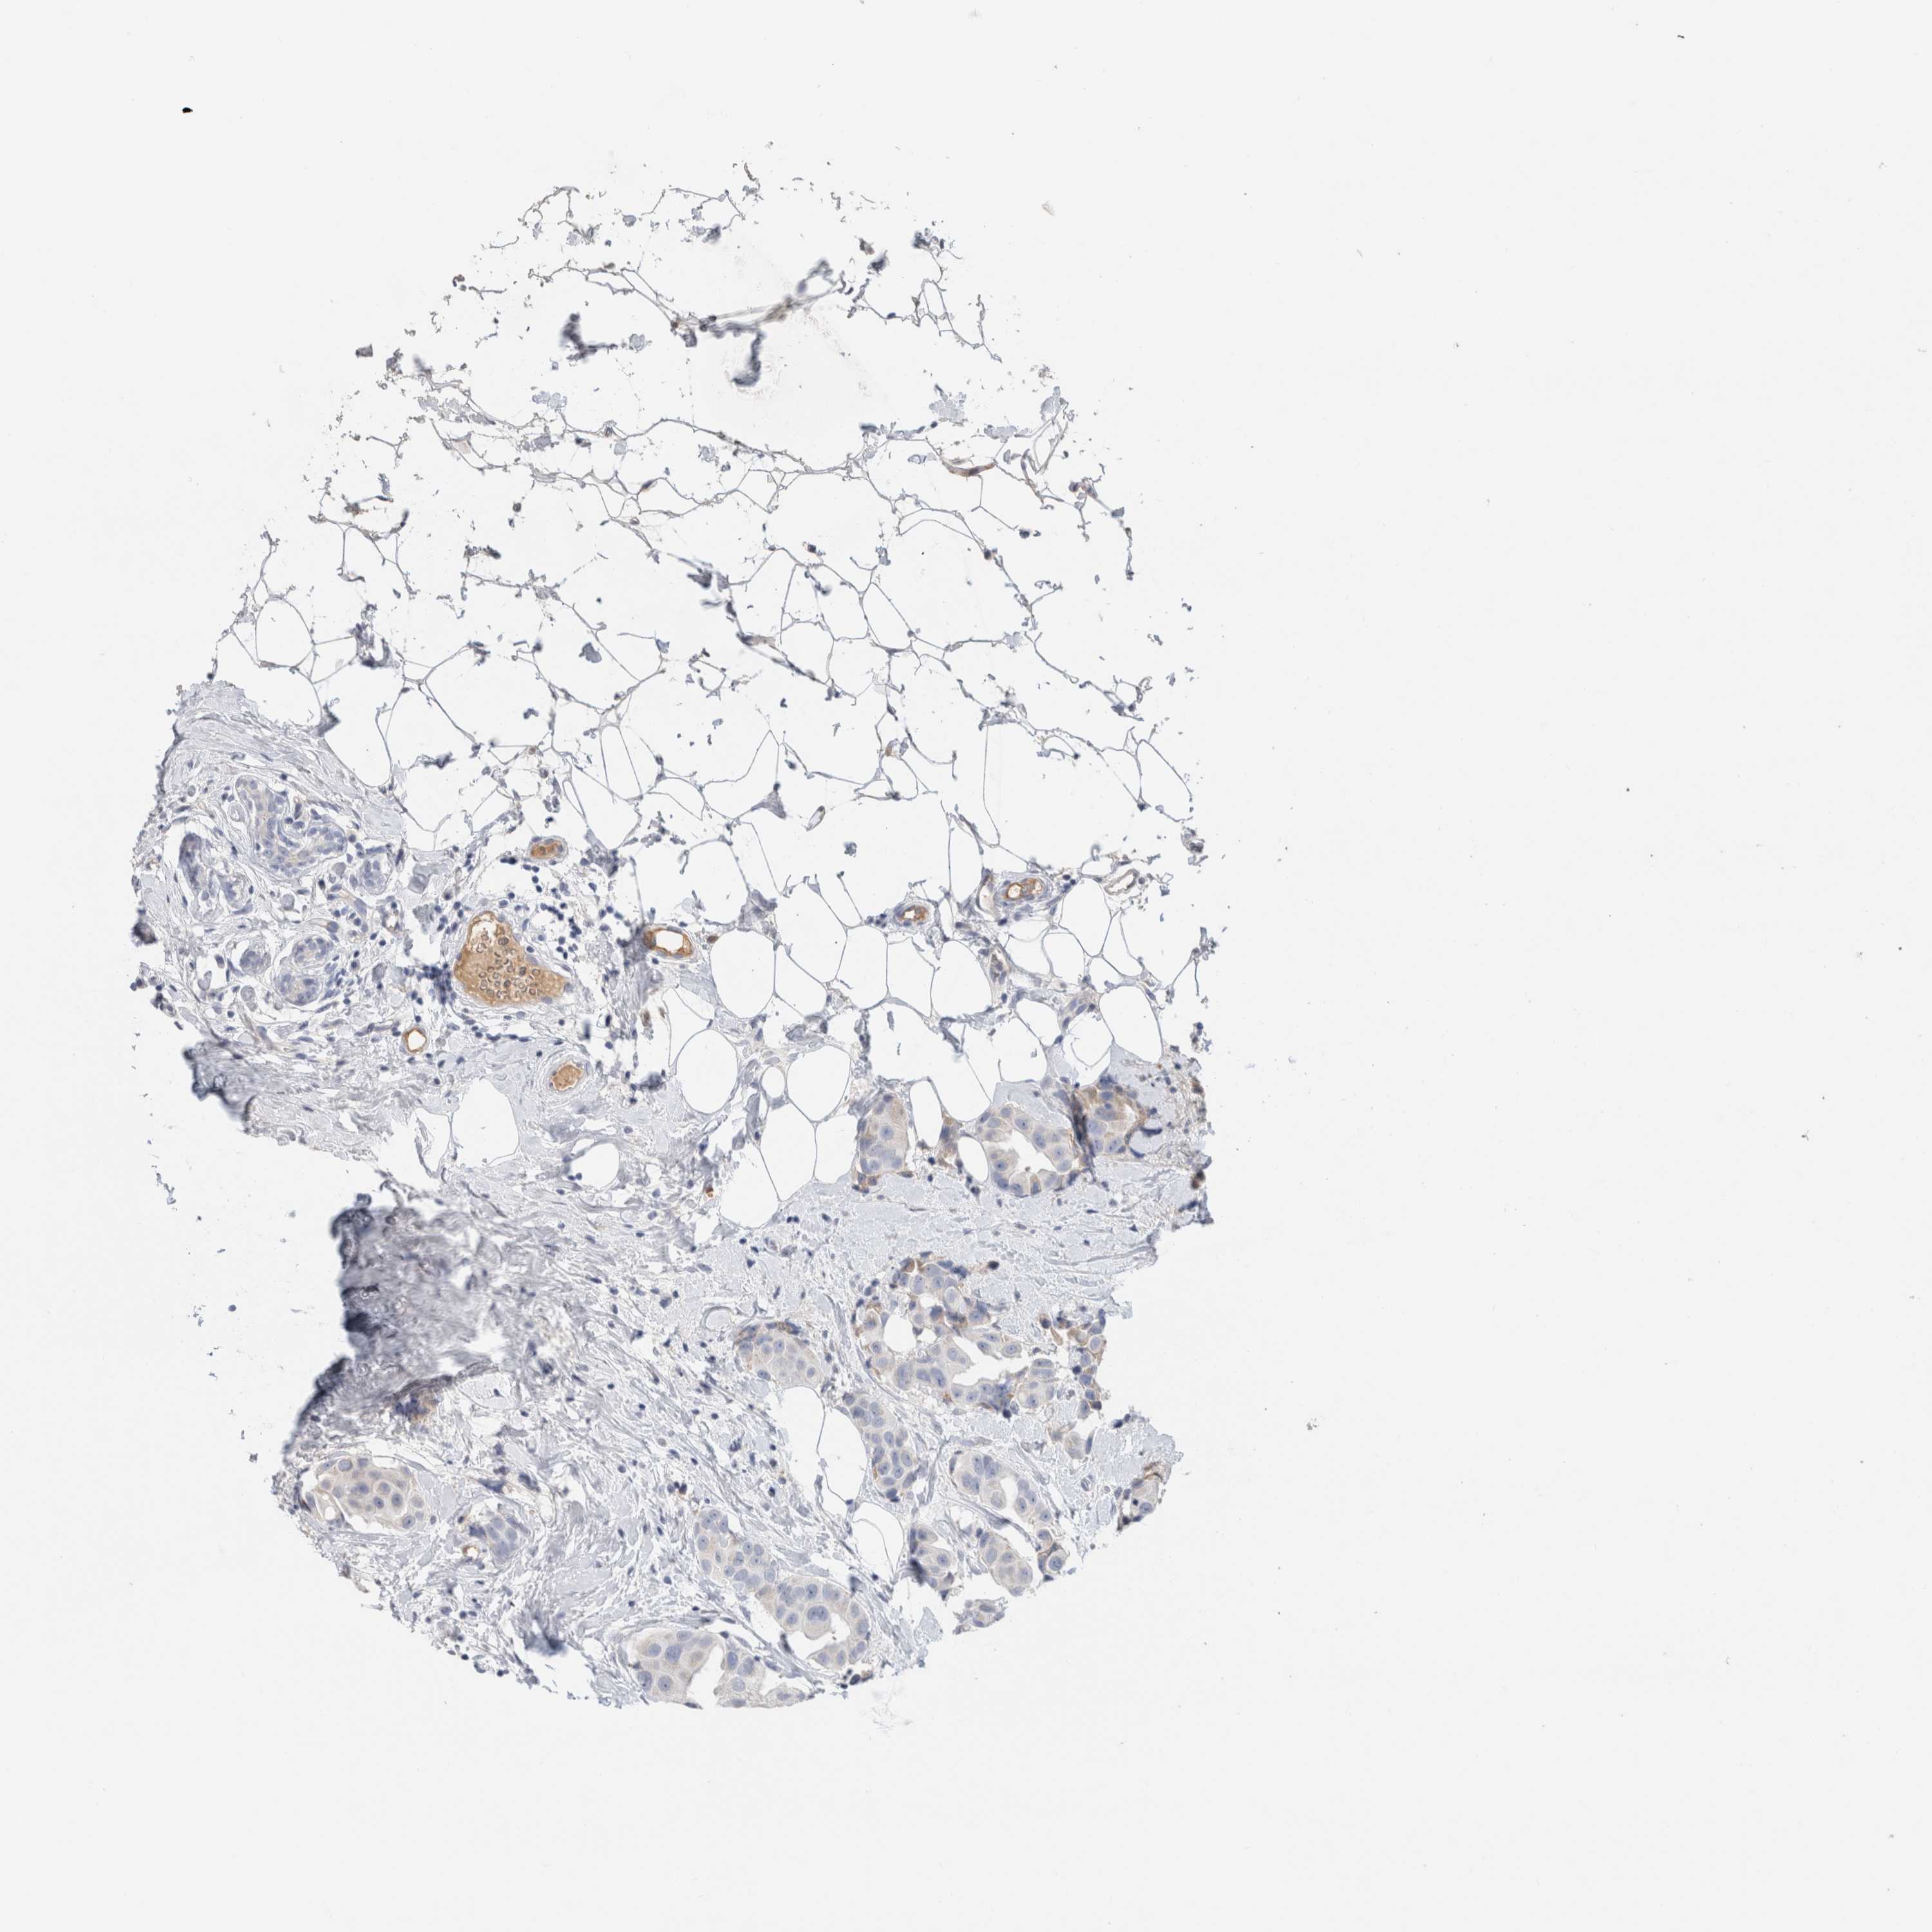

BRCA TCGA BRCA VALIDATION PROTEIN EXPRESSION